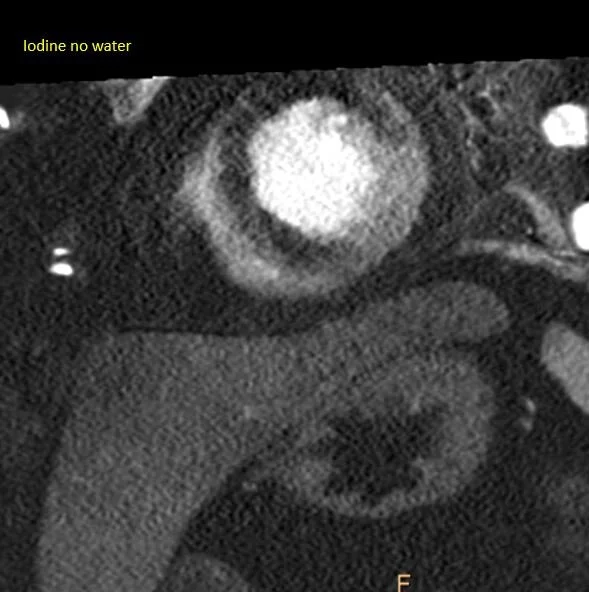

Iodine map